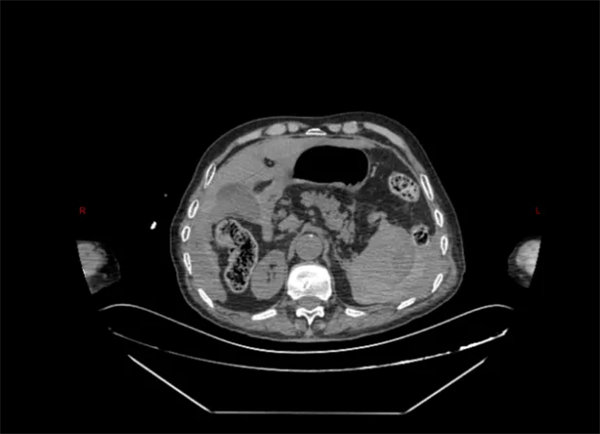

急诊行CT检查提示:脾脏密度不均匀升高,考虑脾破裂。在就诊过程中,患者逐渐出现心率增快,血压降低,行腹腔穿刺抽出不凝血,结合患者既往病情及辅助检查,考虑脾破裂可能性极高。患者病情危重,医院立即启动绿色通道,急诊科、肝胆胰脾外科、麻醉手术科等科室共同协作,将病人由急诊抢救室直接转运至手术室急诊手术治疗。

术中,探查可见患者脾脏包膜下巨大血肿并包裹脾脏,包膜表面可见裂口,并伴有活动性出血,考虑迟发性脾破裂。由于患者年龄较大,必须尽量将手术时间缩短,否则随着手术时间的延长,患者术中术后出现麻醉风险及各类并发症的可能将大大增加。然而,脾脏周围密布着脾动脉、胃短动脉等各式各样的血管,如同布满引线的火药库,想要快速、精准分离脾脏周围组织与血管更是难上加难,任何1毫米的偏差都可能引发难以控制的大出血。患者在术前已经出现休克征象,如果术中再次出现出血等情况,极有可能造成难以挽回的结果。科主任金上博与副主任张晓宾通力合作,凭借高超的手术技术及丰富的手术经验,不到1小时即完成脾脏的切除,整个手术过程也仅仅用时1小时余。术中患者生命体征稳定,病人平稳完成手术。